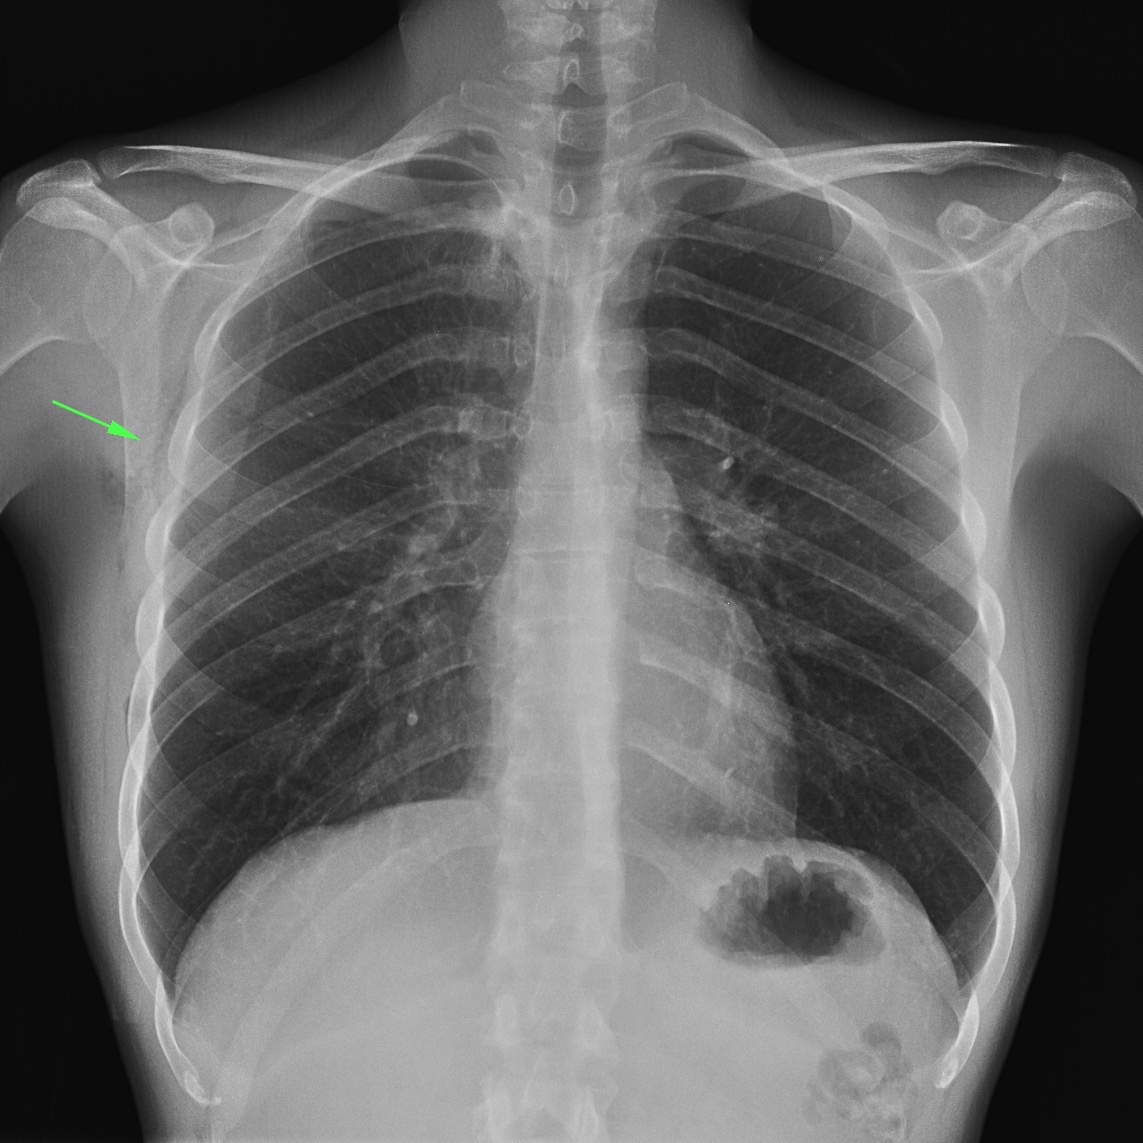

CASO: Operada de esofaguectomia y reconstrucción con coloplastia hace 3 meses. Sintomas de neumonía.

Hallazgos:

- De inicio llama la atención una densidad practicamente total del todo el hemitórax izquierdo, lo cual podría hacernos pensar que estamos ante una posible neumonía.

- Sin embargo el tórax está no está bien centrado, observar como la clavícula izquierda se encuentra casi en la mitad del pulmón, por tanto lo que vemos blanco es el mediastino ya que el tórax está rotado.

CENTRAJE:

El correcto centraje se determina comprobando que las extremidades internas de ambas clavículas equidistan de las apófisis espinosas vertebrales.

Mismo paciente, al cual esta vez se le ha tomado una radiografía en PA y en sedestación. Observar como las clavículas están equidistantes a las apófisis espinosas y como ha desaparecido el velamiento del pulmón izquierdo.

Por otra parte, paciente presenta una cardiomegalia y un discreto ensanchamiento del mediastino es probable relación con cambios postquirúrgicos.